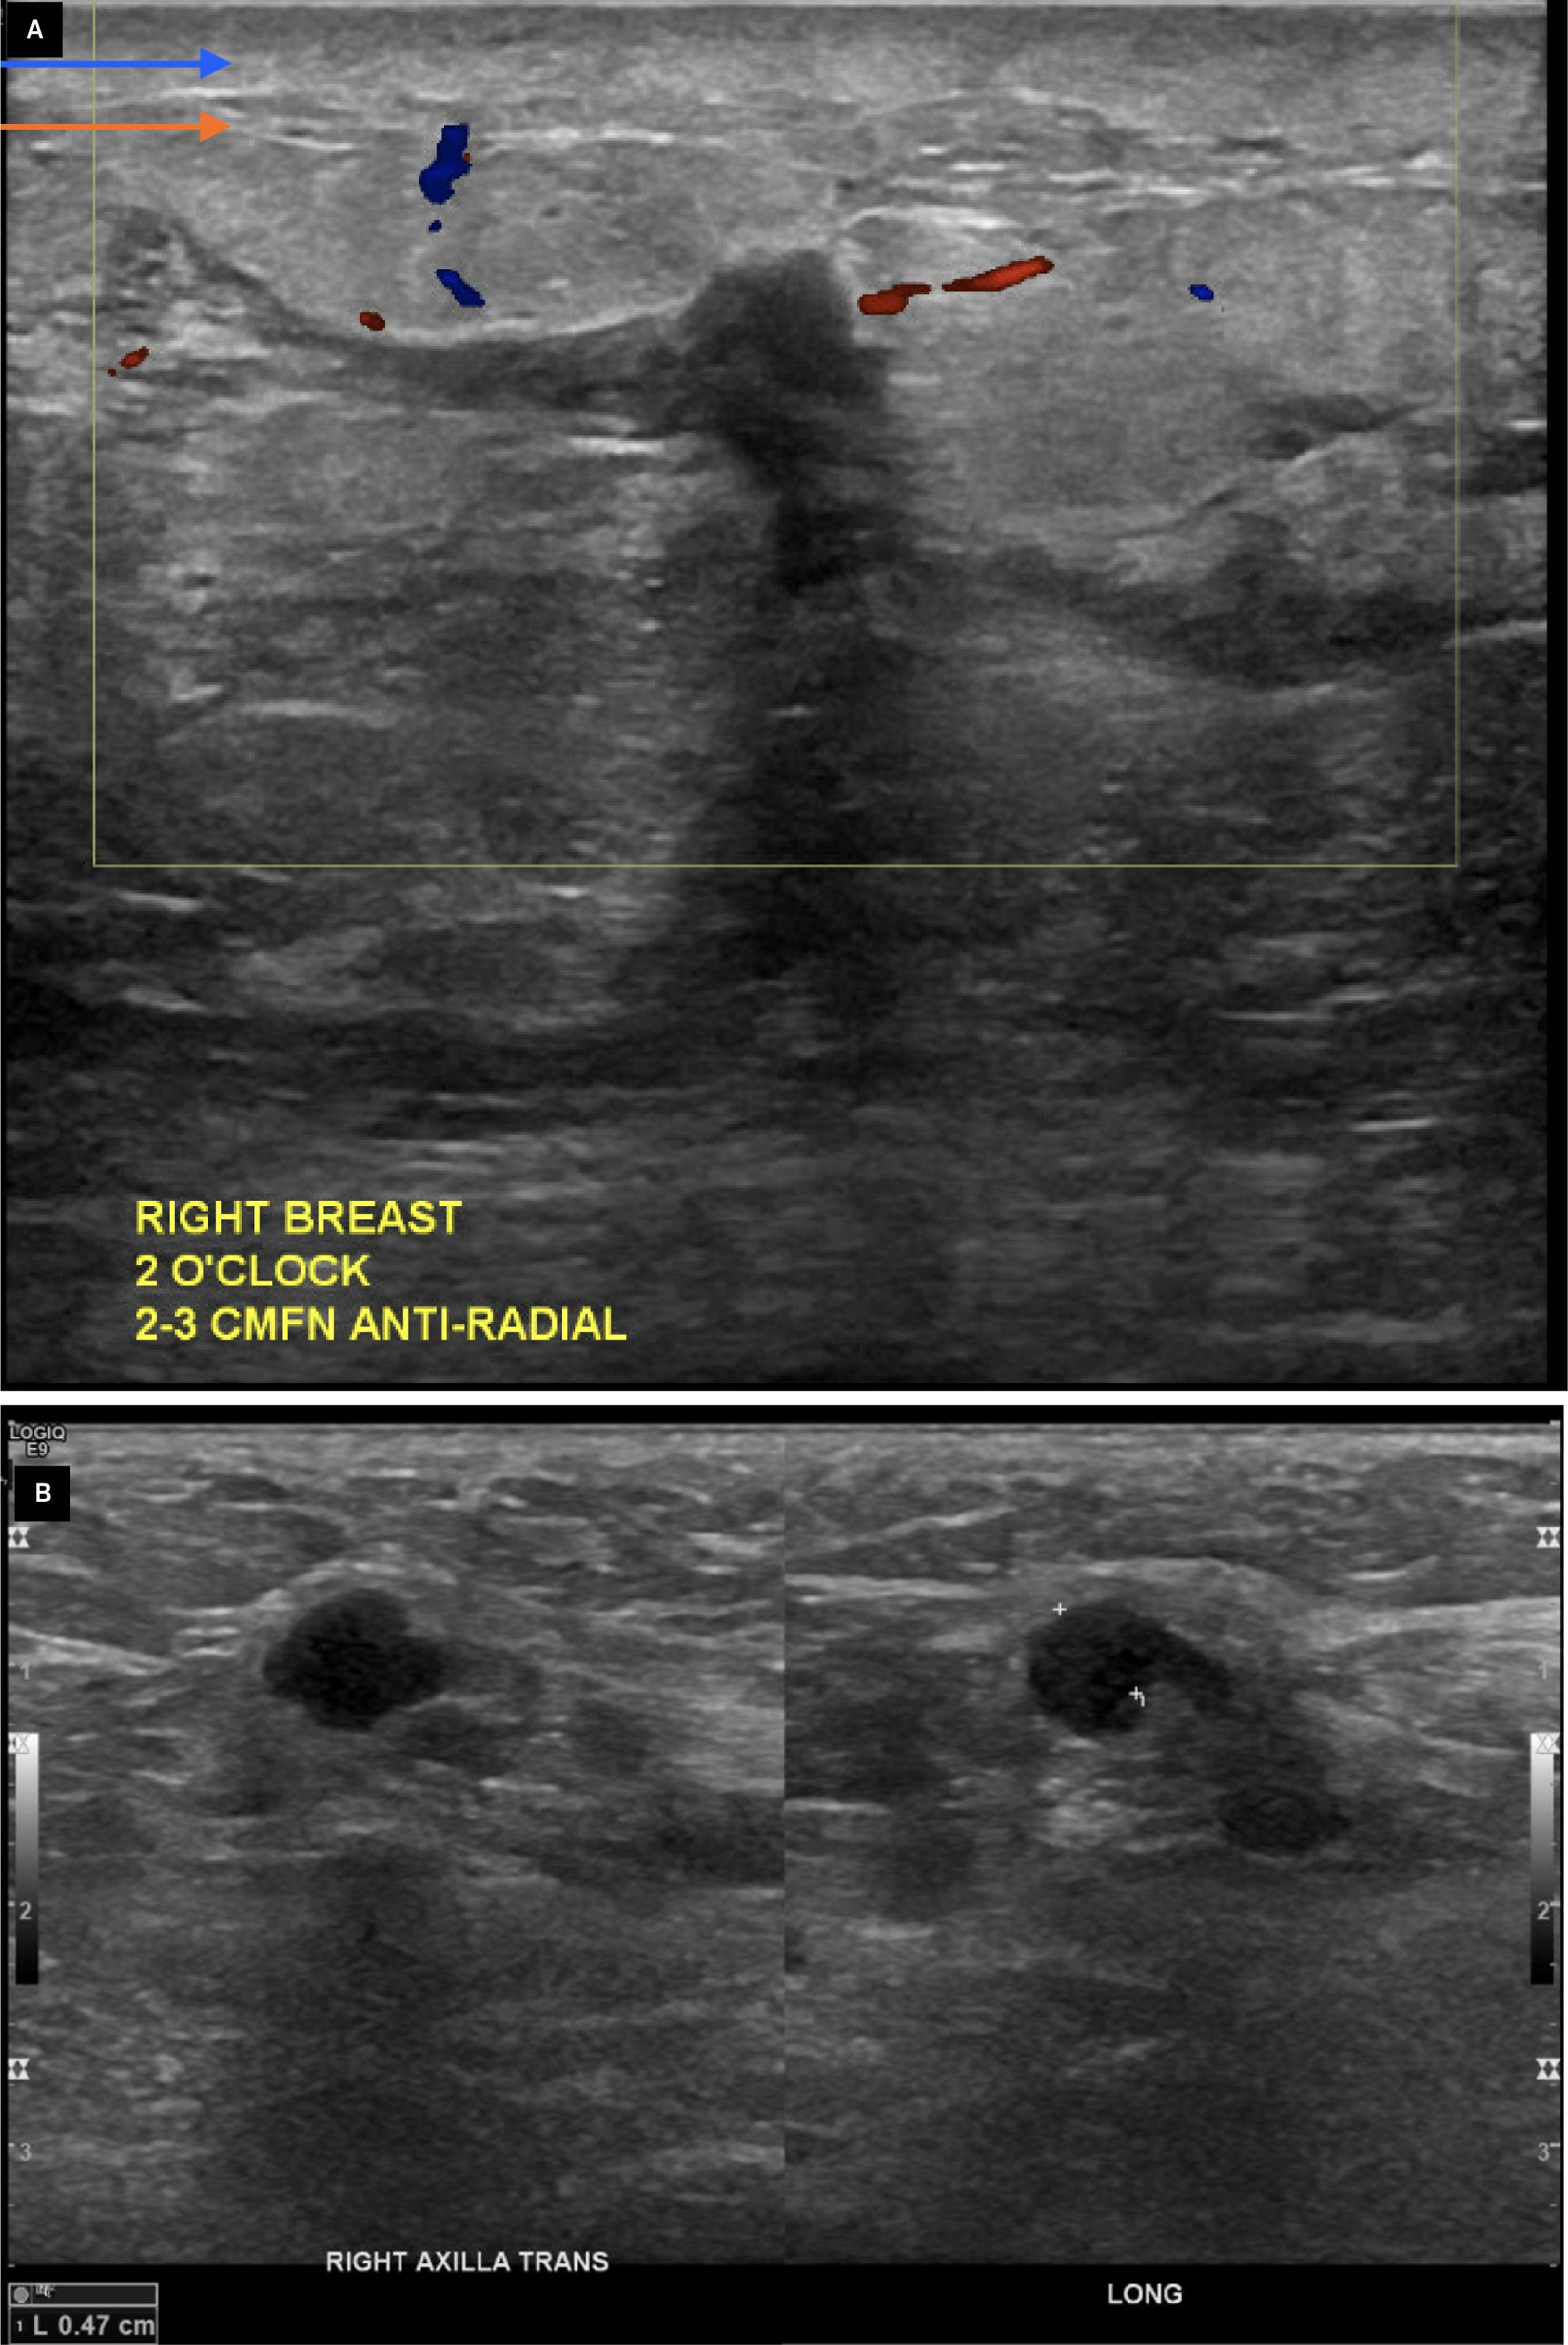

Ultrasound of the right breast revealed marked edema beneath the dermis in nearly every quadrant and below the areola. Additionally, there was an infiltrating appearance of hypoechoic, irregular areas, most prominently seen at 2 o’clock and 6 o’clock positions ( Figure 2A ). Ultrasound of the axilla revealed a mildly prominent lymph node with an eccentrically thickened cortex ( Figure 2B ).

Ultrasound of the right breast imaging shows dermal thickening (blue arrow) with underlying edema (orange arrow), as well as ill-defined hypoechoic collections without discernible Doppler flow (yellow box) at the 2 o’clock position (A). Ultrasound of the right axilla (B) shows a lymph node with an eccentrically thickened cortex (white markers) measuring 0.47 cm and a diminutive fatty hilum.